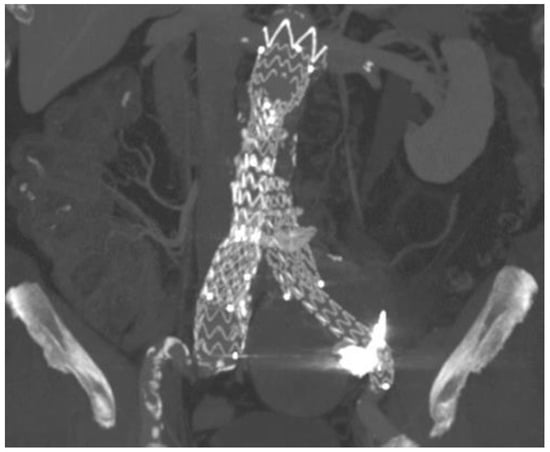

2. Case Presentation

| Present case | Angiographic + DUS guided, 18G needle, sheathless | Sac embolization with coils and a liquid embolic agent | Manual compression | None | 12-month CT scan, stable sac |